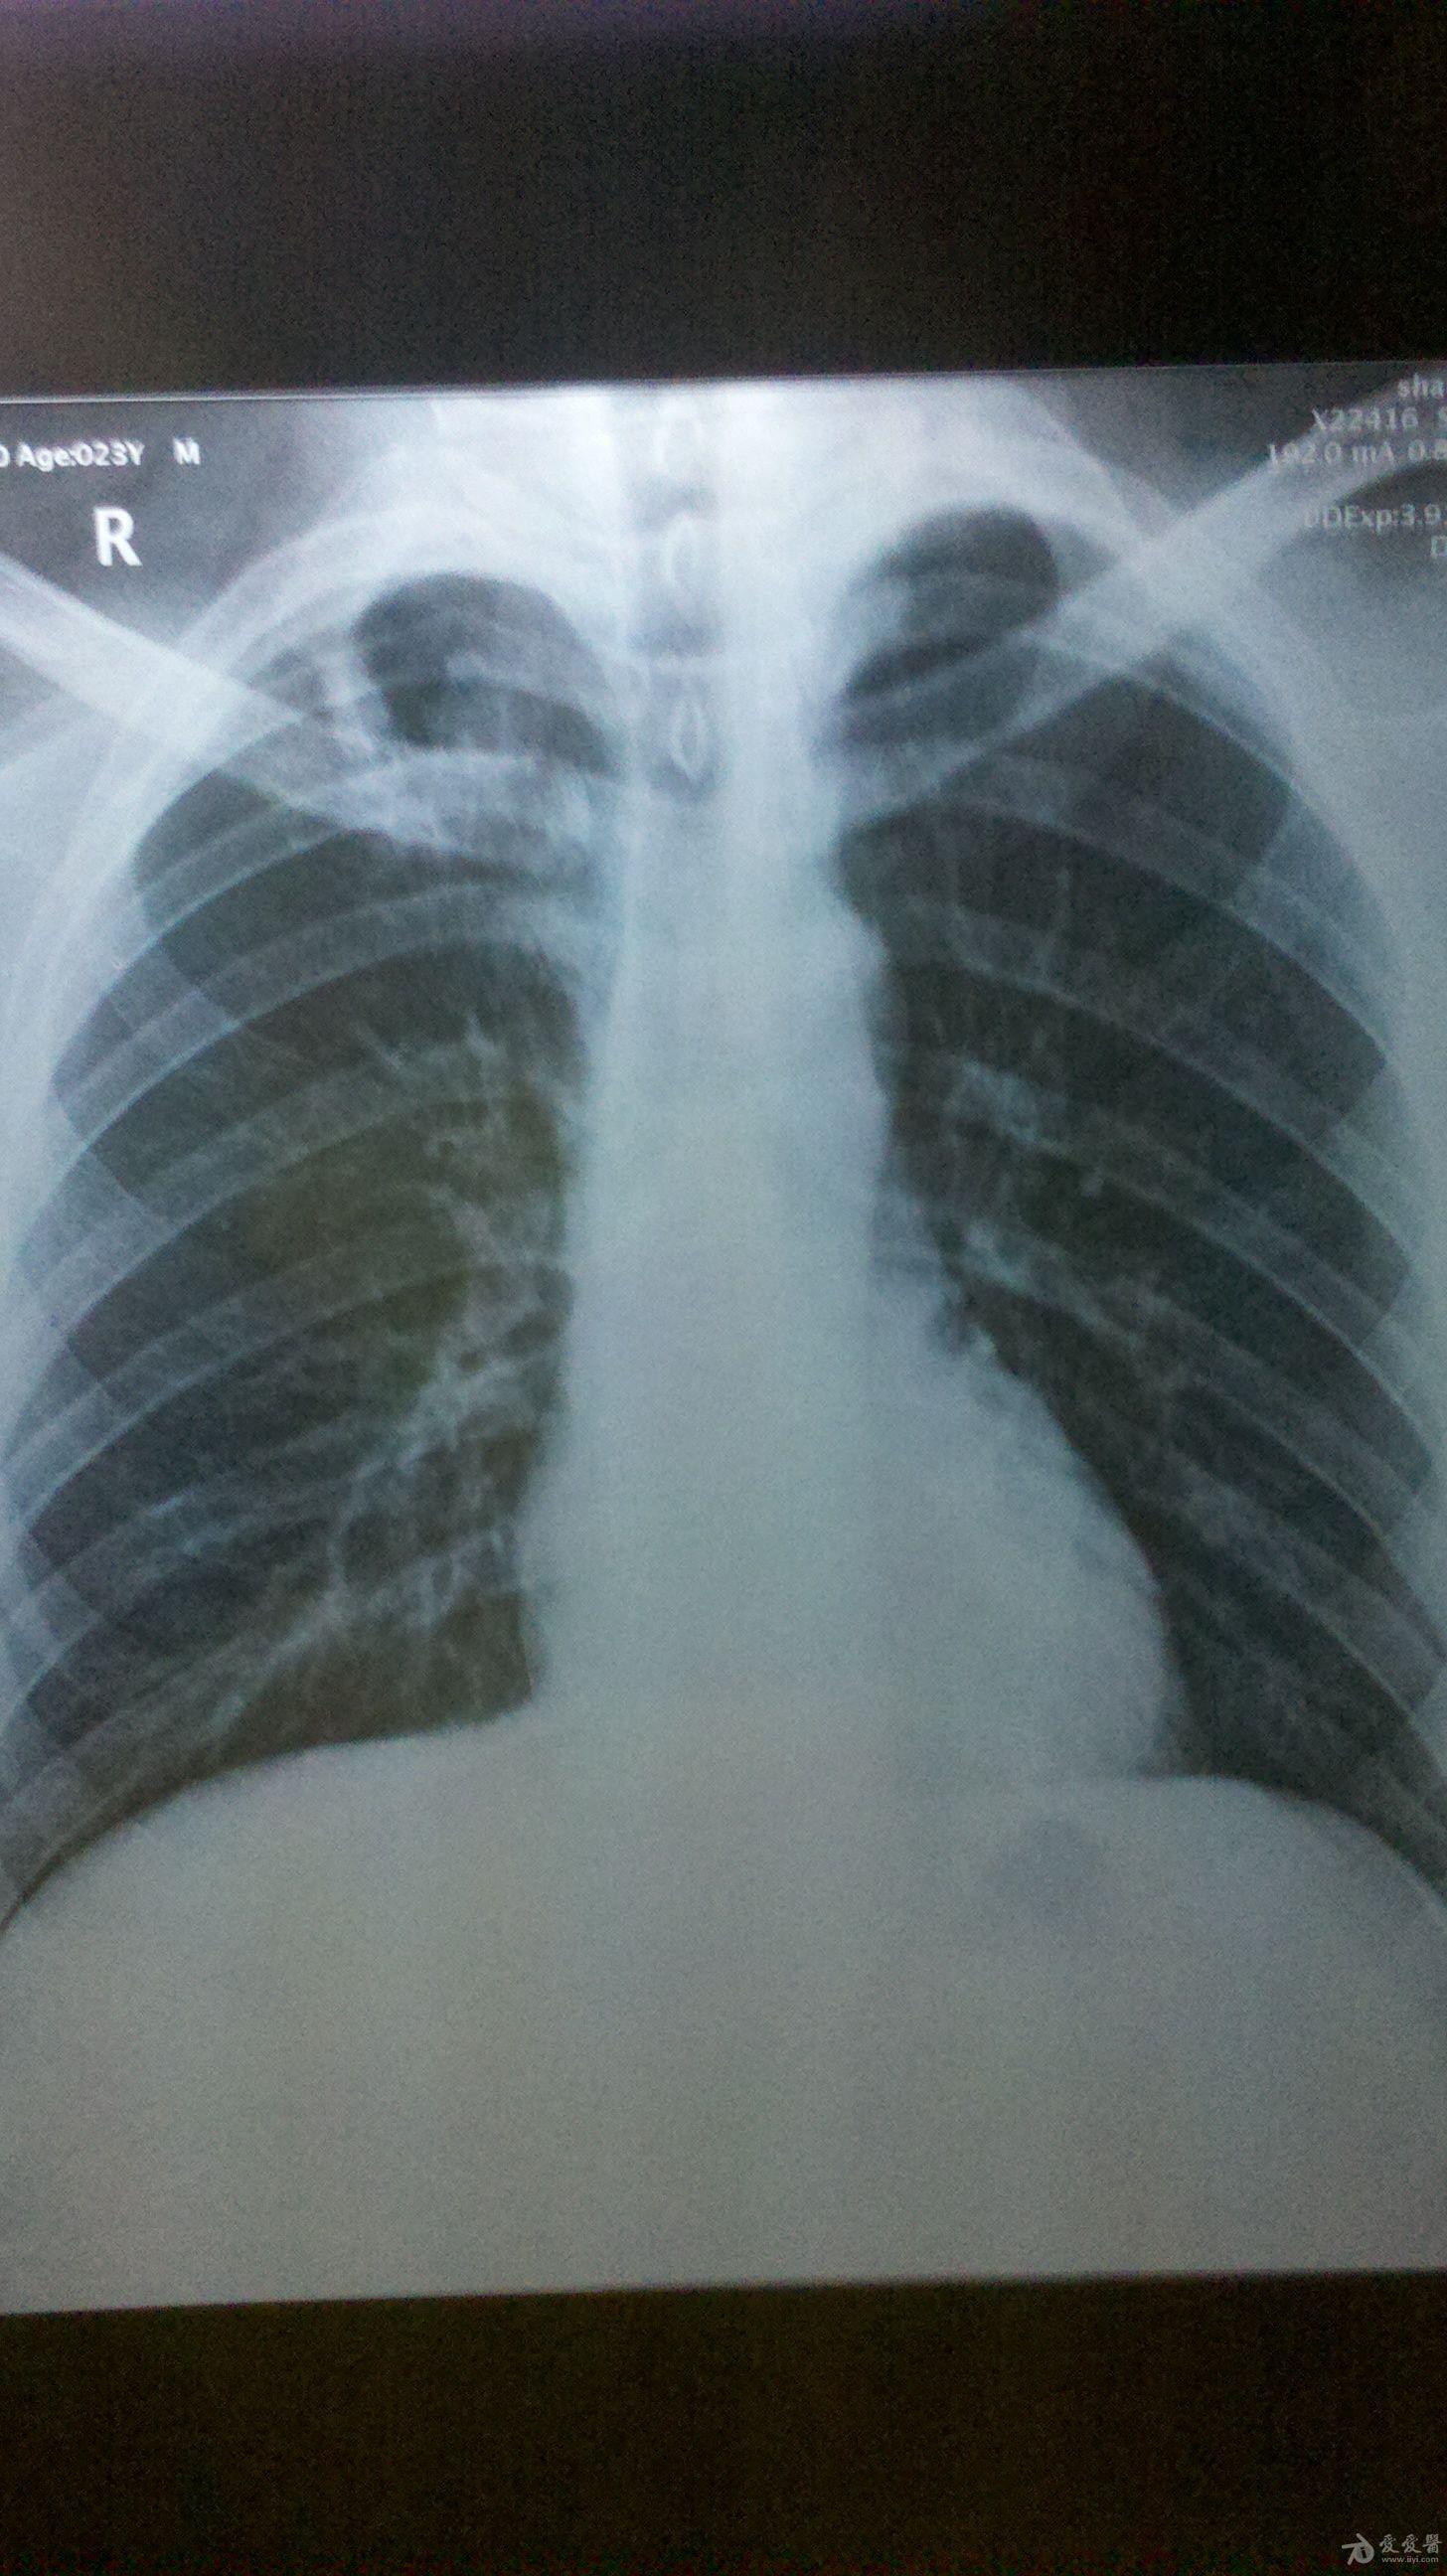

肺结核图片 胸片

肺结核图片 胸片,正常肺与肺结核图片

粟粒型肺结核

患者一年前曾咳嗽3-4个月左右,如今无任何肺结核症状,不咳嗽也不盗汗

肺结核胸片图片

肺结核胸片

肺结核胸片特点